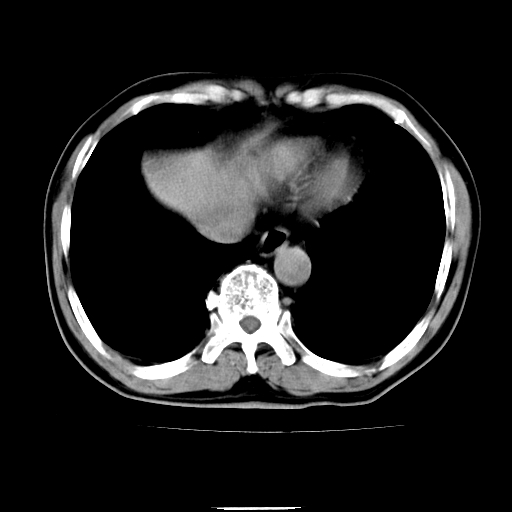

以下是引用chenqiong在2010-3-25 20:56:00的发言:[br]1、胆囊炎,胆囊息肉[br]2、肝内胆管及胆总管扩张,胆总管下端结石[br]3、十二指肠乳头旁憩室

以下是引用zxl51642在2010-3-26 10:47:00的发言:[br]胆囊炎,胆囊息肉,胆总管扩张,但未看到明显肿块,肝内胆管扩张不像恶性,炎性狭窄或阴性结石可能吧,建议mrcp,右肾小囊肿